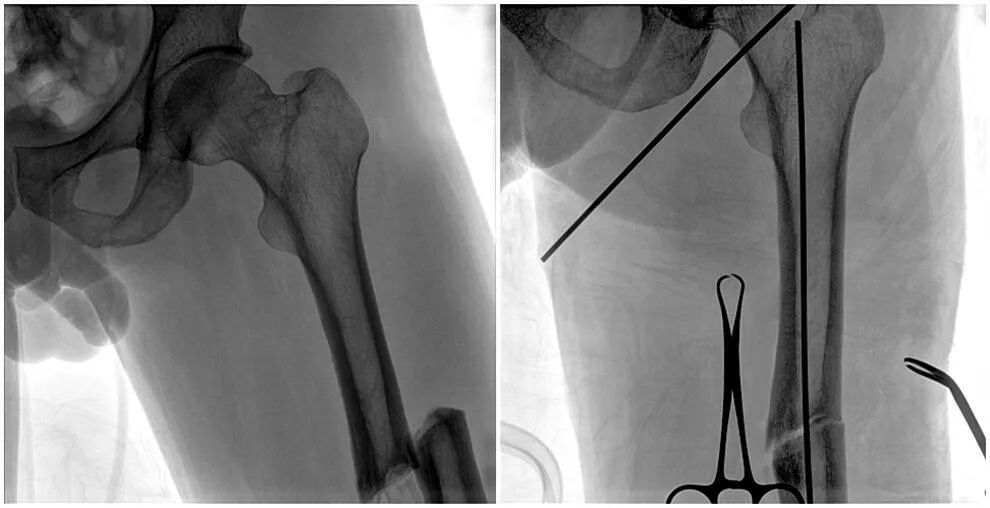

C形臂輔助手術(shù)過程

術(shù)中使用普愛醫(yī)療大平板一體式C形臂進行透視,判斷骨折情況及克氏針、髓內(nèi)釘?shù)冉饘僦踩胛锏奈恢茫M行調(diào)整。C形臂準確的術(shù)中定位,大大縮短了手術(shù)的時間,減輕了患者的痛苦,輔助手術(shù)順利完成。

在進行髓內(nèi)釘內(nèi)固定術(shù)時,醫(yī)生需要同時觀察到入釘點和骨折部位的情況,普愛醫(yī)療大平板一體式C形臂采用30CM×30CM的平板探測器,能夠呈現(xiàn)更廣闊的成像面積,滿足大部分長骨髓內(nèi)釘內(nèi)固定術(shù)的攝片需求。

術(shù)中定位準確、出血量少,術(shù)后影像顯示股骨移位糾正,恢復良好力線,手術(shù)效果良好。